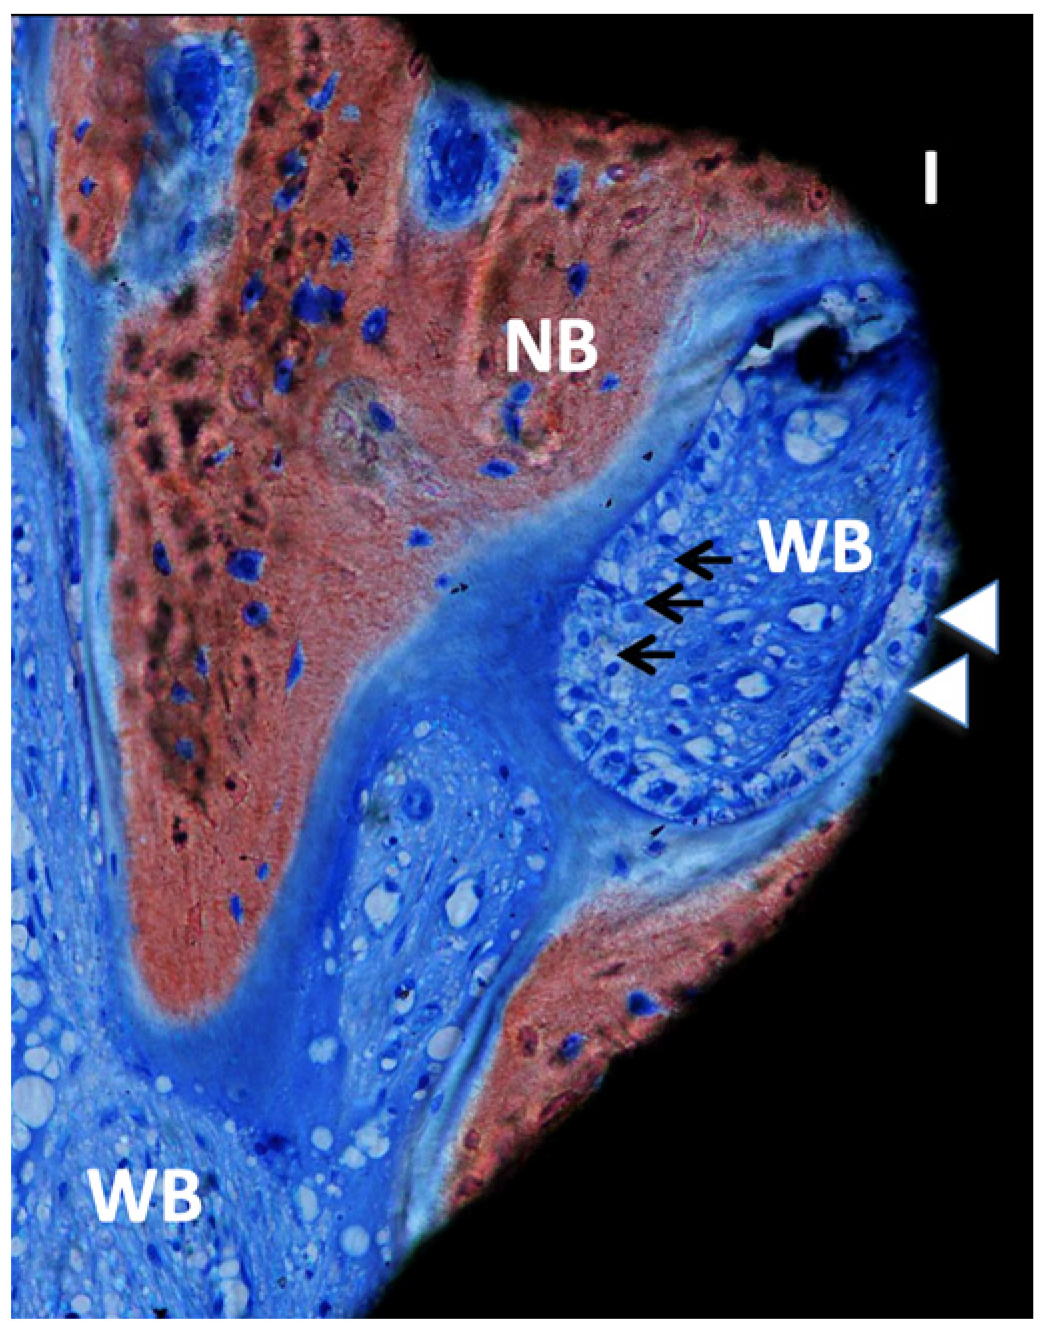

Figure 6.

Ground section—200× original magnification; Stevenel’s blue and alizarin red stain. The implant (I) is in close contact with osteoblasts (white arrowheads), suggesting ongoing bone formation or osseointegration. New bone (NB) is also present with areas of bone matrix formation with several osteoblasts (arrows) and a large area of woven bone (WB), usually seen in the regions with type IV bone (maxillae).